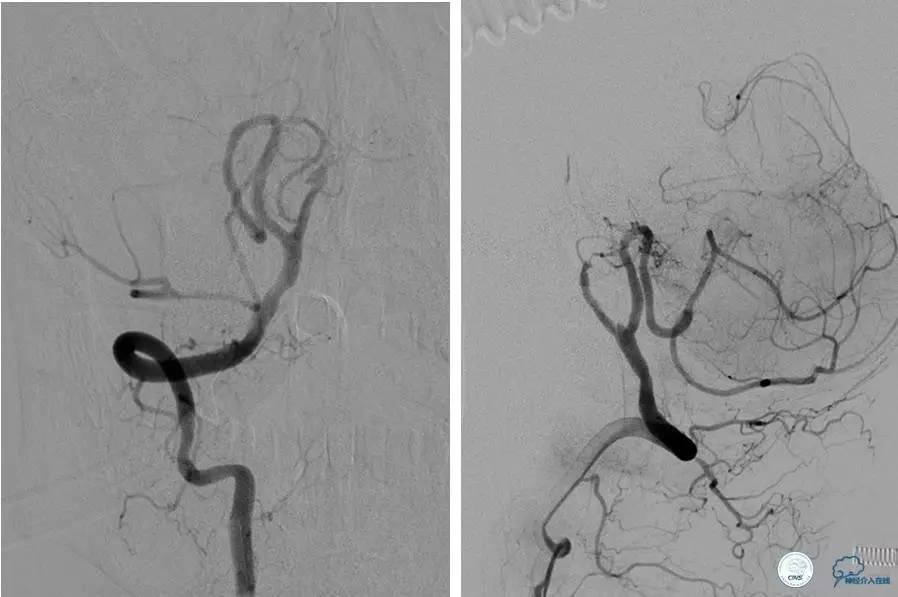

患者:58岁男性,反复头晕、肢体无力3月,当地造影见多发颅内动脉狭窄、闭塞,转来我院。

▼首先行颈动脉CTO开通术,手术顺利,Wallstent支架。

▼1周后行右侧椎动脉V4段CTO开通术。

▼微导丝穿过狭窄段,微导管造影,小球囊预扩张,2mm。

▼根据血管情况选择较大球囊再次预扩张。

▼置入2枚Wingspan支架,手术成功。

▼术后即刻CT,梗死灶内再灌注出血。

患者无症状,中性治疗。4月21日电话随访,一般情况好,当地CT示出血吸收期。